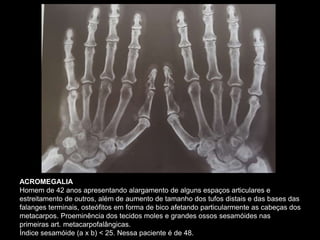

ACROMEGALIA

Homem de 42 anos apresentando alargamento de alguns espaços articulares e

estreitamento de outros, além de aumento de tamanho dos tufos distais e das bases das

falanges terminais, osteófitos em forma de bico afetando particularmente as cabeças dos

metacarpos. Proeminência dos tecidos moles e grandes ossos sesamóides nas

primeiras art. metacarpofalângicas.

Índice sesamóide (a x b) < 25. Nessa paciente é de 48.